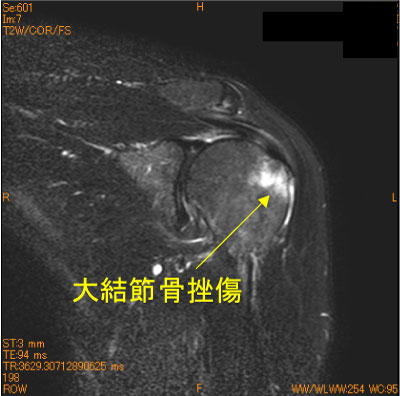

上腕骨大結節骨挫傷-肩関節MRI-

50代女性、自転車で転倒、単純撮影では見えない骨変化。

直達外力による骨損傷だが、安静が不十分だと腱板による牽引により上方に変位する。脂肪抑制T2 WI が有用。

骨挫傷部位は棘上筋腱が単独で付着するsuperior facet。

![]() Obl. Cor T2WI 脂肪抑制 |